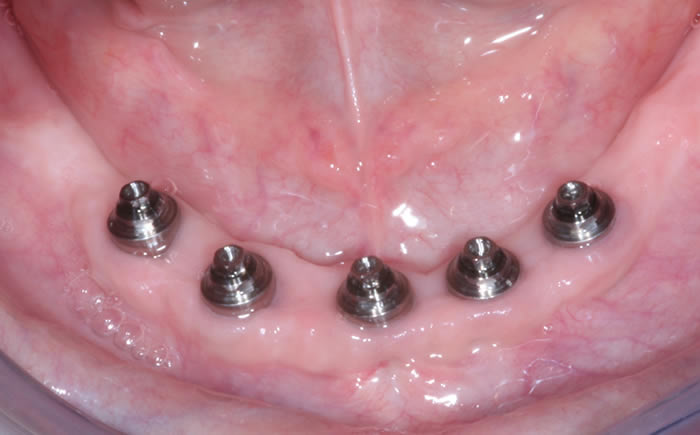

Full arches of teeth replaced by dental implants

Case One (5 images)

Full set of lower teeth fixed onto five dental implants.